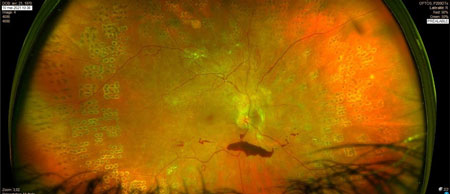

HIV préop

RDP_img11

HIV post op

Ophtalmologie